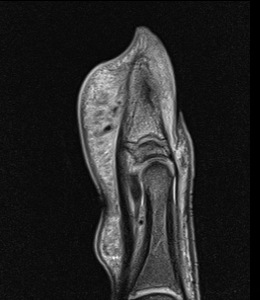

Figure 2 for case Osteoid osteoma ( RID4005 )

Figure 2